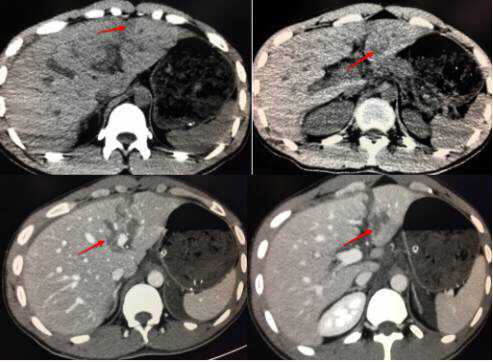

28岁女,车祸入院,怀孕三个月,平扫密度不均匀,增强很大的撕裂口,保守治疗后好转。20天后做了清宫手术。

23岁男,车祸入院,平扫很可能漏掉,调节窄窗宽,密度不均匀,增强很明显撕裂伤。